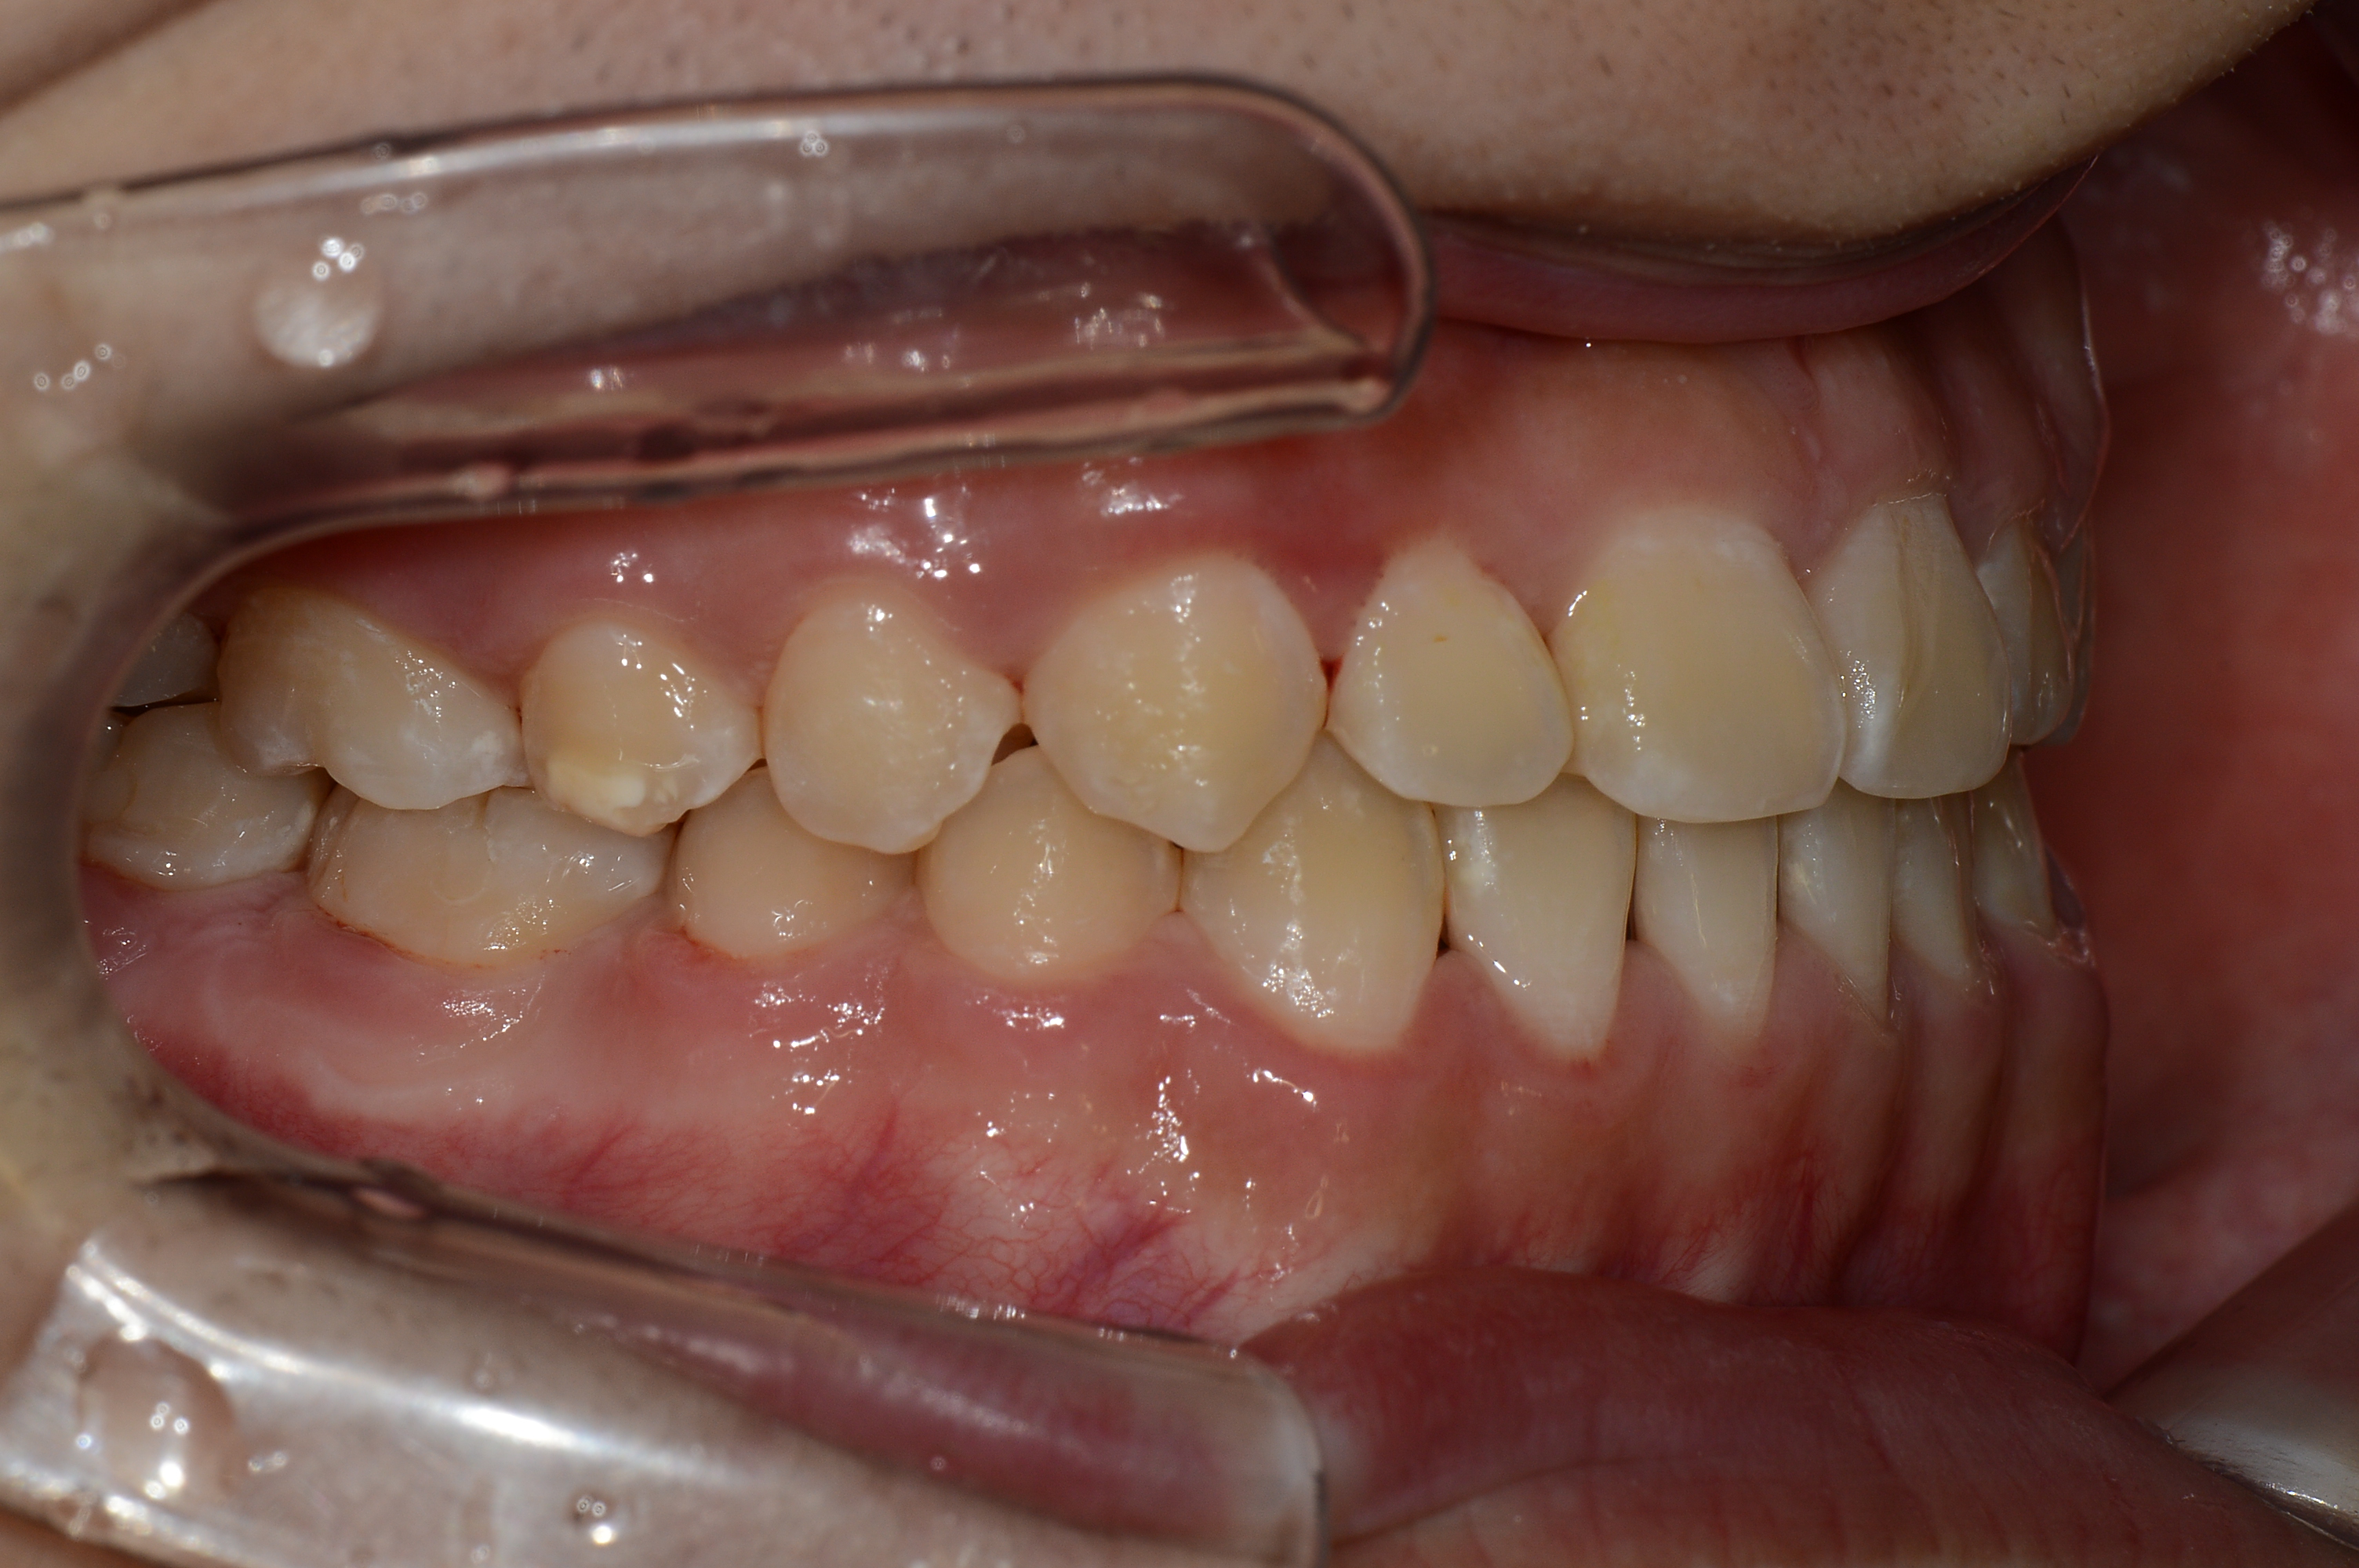

치료 후 사진입니다.